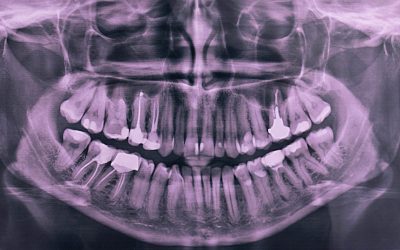

Are dental X-rays safe, and how often should they be taken?

Are Dental X-Rays Safe, and How Often Should They Be Taken? Dental X-rays are a vital part of modern dental care. They help dentists detect issues that are not visible during a regular check-up—like cavities between teeth, bone loss, infections, or impacted teeth. But...